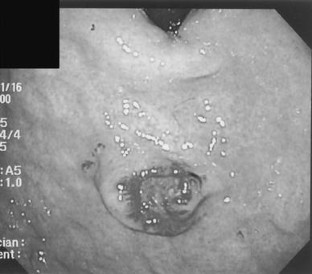

Fig. 4